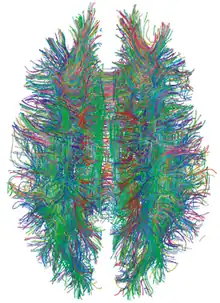

| Diffusion tensor | DTI | Mainly tractography (pictured) by an overall greater Brownian motion of water molecules in the directions of nerve fibers.[82] |

|

Since its development in the 1970s and 1980s, MRI has proven to be a versatile imaging technique. While MRI is most prominently used in diagnostic medicine and biomedical research, it also may be used to form images of non-living objects, such as mummies. Diffusion MRI and functional MRI extend the utility of MRI to capture neuronal tracts and blood flow respectively in the nervous system, in addition to detailed spatial images. The sustained increase in demand for MRI within health systems has led to concerns about cost effectiveness and overdiagnosis.[4][5]